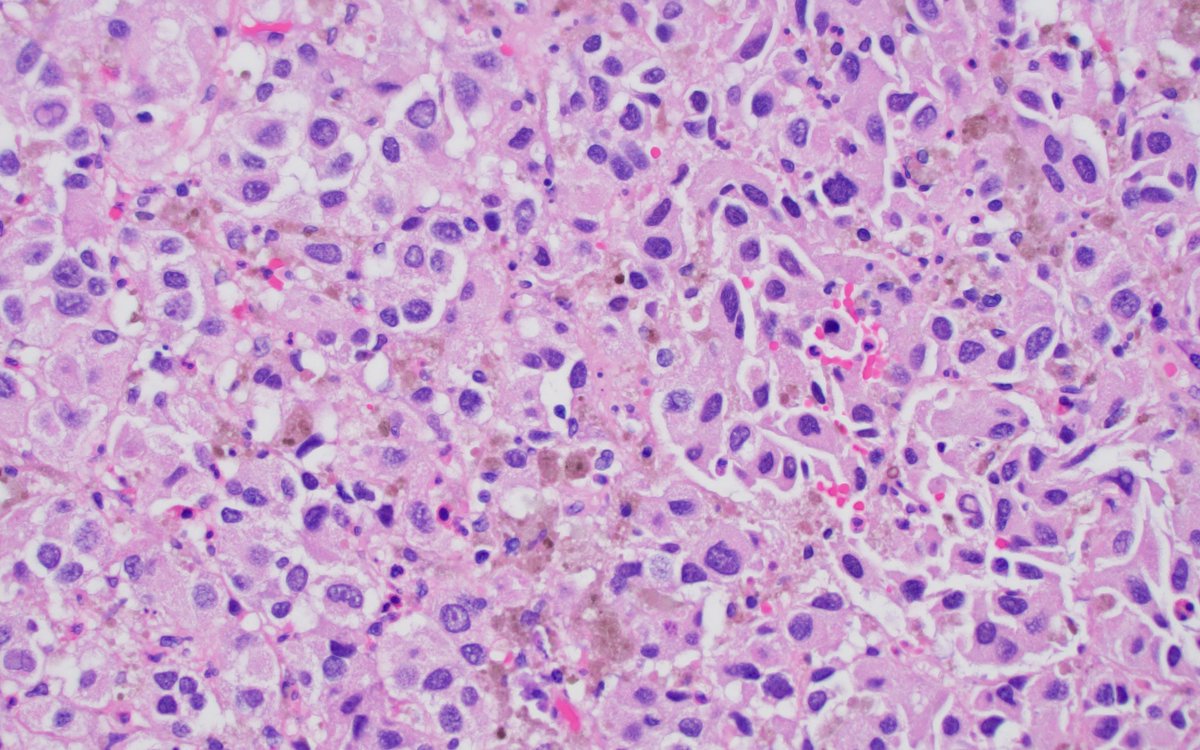

Rare diagnostic pitfall Bladder mass in a 70yo male. Epithelioid cells with focal spindle cell morphology and atypical mitoses, marked variation in nuclear size and shape, hyperchromatic, occasional intranuclear inclusion. Note the absence of in situ carcinoma. see next tweet.

4

49

105

This is a case of metastatic melanoma to bladder. This mass was black in cystoscopy. Less than a 30 are reported in the literature, but the true prevalence is higher, autopsy series on melanoma patients reported 3-18% prevalence. M : F = 15 : 8. #gupath #pathology #bladdercancer

0

16

46